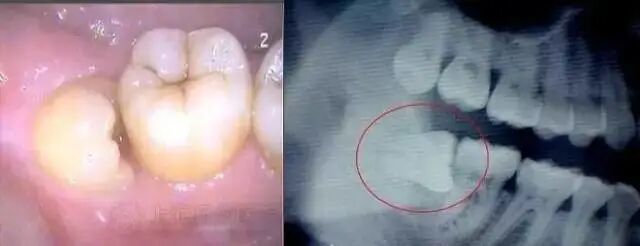

如果智齿位置及方向长得正,而且有良好的咬合关系,就可以考虑保留,但是如果像下面图片所示,牙齿朝前生长,那就要及早拔掉。